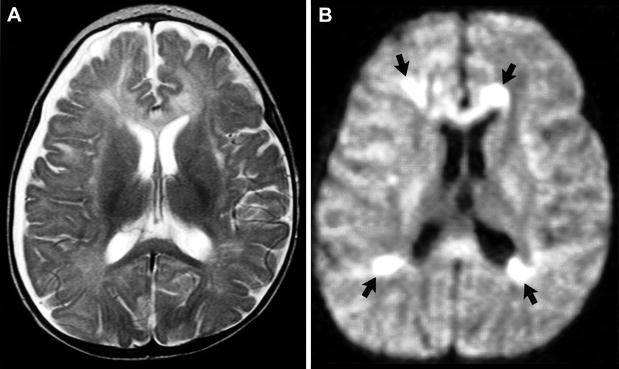

¿Cuál es el mejor estudio de imagen para las complicaciones de la meningitis?

DWI (Difussión weighted imaging)